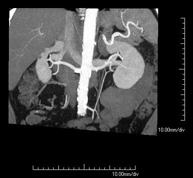

- Angio-TC aorta abdominal  Prueba diagnóstica no invasiva que consiste en el estudio de la arteria aorta abdominal obteniendo imágenes de alta definición anatómica mediante el empleo de un equipo de TC (Tomografía Computarizada) y de contraste yodado. La calidad de las imágenes permite realizar reconstrucciones en 2D y 3D gracias a estaciones de trabajo especializadas en el estudio arterial. Está indicado en aquellos pacientes con enfermedad vascular (aterosclerosis), en aneurismas de aorta, en pacientes con dolor abdominal de posible origen vascular, en estudios pre-quirúrgicos de lesiones adyacentes a la aorta abdominal como "mapa" vascular, etc. La información obtenida de forma no invasiva es indispensable para los pacientes que requieren tratamiento percutáneo o quirúrgico. En aquellos pacientes que solo requieren un seguimiento de las lesiones vasculares, esta técnica es la técnica no invasiva de elección junto con la angio-RM. Prueba diagnóstica no invasiva que consiste en el estudio de la arteria aorta abdominal obteniendo imágenes de alta definición anatómica mediante el empleo de un equipo de TC (Tomografía Computarizada) y de contraste yodado. La calidad de las imágenes permite realizar reconstrucciones en 2D y 3D gracias a estaciones de trabajo especializadas en el estudio arterial. Está indicado en aquellos pacientes con enfermedad vascular (aterosclerosis), en aneurismas de aorta, en pacientes con dolor abdominal de posible origen vascular, en estudios pre-quirúrgicos de lesiones adyacentes a la aorta abdominal como "mapa" vascular, etc. La información obtenida de forma no invasiva es indispensable para los pacientes que requieren tratamiento percutáneo o quirúrgico. En aquellos pacientes que solo requieren un seguimiento de las lesiones vasculares, esta técnica es la técnica no invasiva de elección junto con la angio-RM.

- Angio-TC arterias renales  Prueba diagnóstica no invasiva que consiste en el estudio de las arterias renales obteniendo imágenes de alta definición anatómica mediante el empleo de un equipo de TC (Tomografía Computarizada) y de contraste yodado. La calidad de las imágenes permite realizar reconstrucciones en 2D y 3D gracias a estaciones de trabajo especializadas en el estudio arterial. Esta prueba está indicada, por ejemplo, en aquellos pacientes que sufren de HTA refractaria al tratamiento, en pacientes con lesiones renales para tener un mapa "vascular" pre-quirúrgico, etc. Prueba diagnóstica no invasiva que consiste en el estudio de las arterias renales obteniendo imágenes de alta definición anatómica mediante el empleo de un equipo de TC (Tomografía Computarizada) y de contraste yodado. La calidad de las imágenes permite realizar reconstrucciones en 2D y 3D gracias a estaciones de trabajo especializadas en el estudio arterial. Esta prueba está indicada, por ejemplo, en aquellos pacientes que sufren de HTA refractaria al tratamiento, en pacientes con lesiones renales para tener un mapa "vascular" pre-quirúrgico, etc.

- Angio-TC aorto-ilíaco Prueba diagnóstica no invasiva que consiste en el estudio de las arterias ilíacas y la aorta abdominal obteniendo imágenes de alta definición anatómica mediante el empleo de un equipo de TC (Tomografía Computarizada) y de contraste yodado. La calidad de las imágenes permite realizar reconstrucciones en 2D y 3D gracias a estaciones de trabajo especializadas en el estudio arterial. Esta prueba está especialmente indicada como estudio pre-quirúrgico (mapa vascular) antes de intervenciones percutáneas o quirúrgicas de aorta abdominal, como el estudio complementario en pacientes con isquemia de miembros inferiores, etc. Prueba diagnóstica no invasiva que consiste en el estudio de las arterias ilíacas y la aorta abdominal obteniendo imágenes de alta definición anatómica mediante el empleo de un equipo de TC (Tomografía Computarizada) y de contraste yodado. La calidad de las imágenes permite realizar reconstrucciones en 2D y 3D gracias a estaciones de trabajo especializadas en el estudio arterial. Esta prueba está especialmente indicada como estudio pre-quirúrgico (mapa vascular) antes de intervenciones percutáneas o quirúrgicas de aorta abdominal, como el estudio complementario en pacientes con isquemia de miembros inferiores, etc.